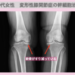

痛み10段階中5が1に!10年悩んだ両膝の痛みから解放 10年間両膝の痛みに苦しみ、立っていることも辛くなって人工関節を勧められていた60代の患者様。“リペア幹細胞”によって痛みが劇的に軽減しました。両膝とも10段階中5だった痛みが1まで改善し、人工関節を回避してアクティブな活動を続けられるようになったのです。 まだまだ元気に動きたいと願っていた患者様が、このような回復を実現できたのは、いったいどのような治療だったのでしょうか。 治療前の状態 10年前から両膝関節痛に悩む 痛み止めを飲みながら過ごしてきた 最近では立っていることも辛い 痛みは両膝とも10段階中5で人工関節を勧められる この患者様は、10年前からの両膝関節痛のため受診していただきました。当時、近くの整形外科で変形性膝関節症と診断されたそうです。以後、痛み止めを飲みながら過ごしてきましたが、最近では立っていることも辛くなってしまいました。レントゲンを再度撮影すると、軟骨のすり減りが進行しており、医師から人工関節を勧められました。まだまだアクティブな活動を続けたい患者様は人工関節を躊躇し、軟骨を再生させる方法を探され、幹細胞治療に辿り着いて当院を受診されました。 一旦人工関節になると、耐用性の問題から活動的に動き回ることができなくなりますし、膝の可動域の制限も出てしまいます。入院期間、合併症のリスク、術後の痛みなども懸念されます。 “リペア幹細胞”とリペアセルクリニックの特徴 詳細については、こちらで当院独自の再生医療の特徴を紹介しています。 リペアセルクリニックは「膝の痛み」に特化した再生医療専門クリニックです。手術・入院をしない新たな治療【再生医療】を提供しております。 レントゲン所見 レントゲンにて関節の狭小化を認めます。 <治療内容>両膝に“リペア幹細胞”1億個を3回投与+PRP 両膝に“リペア幹細胞”1億個を3回投与いたしました。 治療後の変化 両膝の痛みが10段階中5から1へ劇的に改善 立っていることが辛かった状態から解放 人工関節を回避してアクティブな活動を継続 10年間の悩みから解放 最終投与後には両膝とも投与前10段階中5だった痛みが1まで軽減しました。“リペア幹細胞”が両膝の軟骨欠損部位に直接働きかけ、投与する度に一層ずつ軟骨が再生されていったことで、このような素晴らしい改善が実現したのです。10年間痛み止めを飲みながら耐えてきた痛みから解放され、人工関節を回避してアクティブな活動を続けられるようになりました。 変形性膝関節症で人工関節を回避したい方、まだまだアクティブな活動を続けたい方に、当院の再生医療は新たな可能性を提供します。膝の痛みでお悩みの方はぜひ一度、当院へご相談ください。 当院独自の“リペア幹細胞”、そして国内で珍しい分化誘導技術を用いた“リペア幹細胞プラス”で、『次世代の再生医療』を提供します。 <治療費> 関節1部位 幹細胞数 ( 2500万個~1億個) 投与回数( 1回 )132万円( 税込 )/2500万個 分化誘導( 1回 )55万円( 税込 ) PRP治療 16.5万円(税込) <起こりうる副作用> 脂肪採取部の内出血や創部感染、傷跡などが起こることがあります。 症状によりMRIやCTなどの検査を受けて頂く事があります。 ※こちらでご紹介している症例は一部の患者様です。掲載以外の症例も多数ございます。ご自身の症状については、お気軽にご相談ください。 変形性膝関節症の再生医療についてはこちらで詳しく説明しています。↓ 再生医療医師監修:黄金勲矢